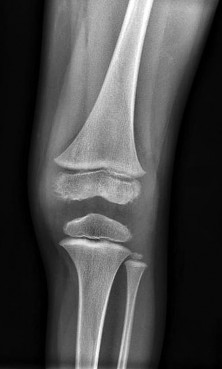

A 3-year-old girl, who is at the 95th percentile for weight and began walking at 9 months of age, presents with progressive bilateral genu varum.

Radiographs reveal an abrupt medial beaking of the proximal tibial metaphysis and a metaphyseal-diaphyseal angle (Drennan's angle) of 18 degrees. What is the most likely diagnosis?